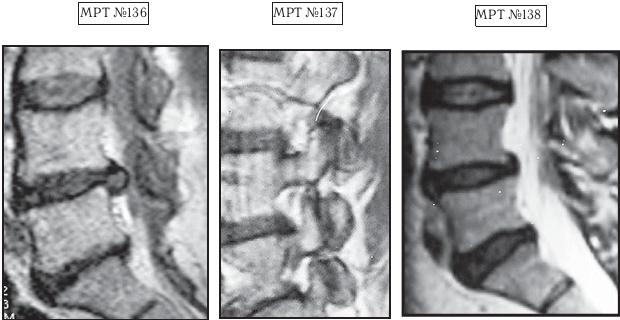

МРТ № 3

На МРТ № 3 — поясничный отдел позвоночника. (На данном «контрольном» снимке наблюдаются остаточные явления дегенеративно-дистрофического процесса в сегменте LV-SI после устранения методом вертеброревитологии секвестрированной грыжи межпозвонкового диска.)

В поясничном отделе форма позвоночного канала, создаваемая телом и дужками позвонка, вариабельна, но чаще она пятиугольная. В норме позвоночный канал в пояснично-крестцовом отделе сужен в переднезаднем диаметре на уровне LIII и LIV позвонков. Его диаметр каудально увеличивается, и поперечное сечение канала приобретает форму, близкую к треугольной, на уровне LV-SI. У женщин канал имеет тенденцию к расширению в нижней части крестцовой области. Сагиттальный диаметр значительно уменьшается от LI к LIII почти неизменен от LIII к LIV и увеличивается от LIV к LV. В норме переднезадний диаметр позвоночного канала в среднем равен 21 мм (15–25 мм).

Существует простая и удобная формула определения ширины позвоночного канала:

нормальный сагиттальный размер не менее 15 мм;

11–15 мм — относительный стеноз;

менее 10 мм — абсолютный стеноз. Уменьшение этого соотношения свидетельствует о сужении канала.

Высота поясничных межпозвонковых дисков 8–12 мм, нарастает от LI до LIV-LV, обычно уменьшается на уровне LV-SI